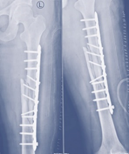

Case-I

19 years, male;

Broken ILIMN of femur (Ipsilateral fracture shaft of femur with tibia and fibula, H/O-poly-trauma) (Figure 1-4). Infection and non-union are the morbid complications of fracture management. Infections are more common in open fracture also caused by superficial surgical site infection. The incidence of infection in closed long bones fracture 1-2% and it is higher in open fracture, 5% Gustilo type-Ⅰ, 10% Gustilo type-Ⅱ and 15% Gustilo type-Ⅲ8 and surgical site infection (SSI) is 3.6 to 4.8%.9 The fracture complexity and soft tissue damage are the critical factors, influence the risk of infection.

Figure 1 X-ray broken IM nail after fall.

Figure 2&3 Post-operative x-ray after Ilizarov operation.

Figure 4 X-ray after union.